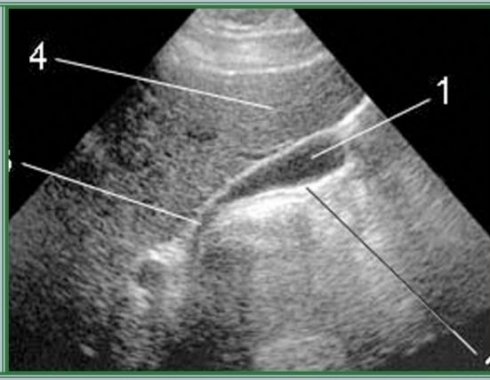

Исследование функции желчного пузыря с нагрузкой. Включает 4 осмотра — натощак, через 5 мин., через 20 мин. и через 45 мин. после приема пробного завтрака (раствор сорбита; для детей — раствор хофитола). Больного обследуют в нескольких позициях — обязательно в положении на спине и на левом боку. После исследования врач производит оценку графика сокращения желчного пузыря и на основании полученных данных делает вывод о типе функциональных расстройств.

Показания — дискинезия желчевыводящих путей. Метод позволяет различить 5 типов дискинезий для выбора правильного лечения. Проводится натощак, не разрешается принимать пищу 6 — 8 часов до исследования, пить 2 часа до исследования.